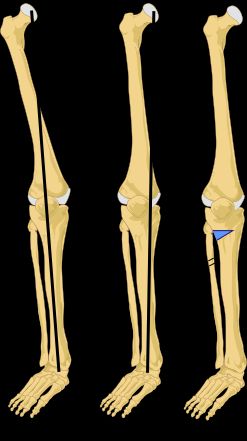

내반슬은 다리가 휜 상태를 의미하며, 어린이나 성인에게 나타날 수 있다. 주요 원인으로는 구루병, 골격 문제, 감염, 종양, 외상 등이 있으며, 특히 기수에게서 직업적 요인으로 나타나기도 한다. 어린이는 생리적으로 내반슬을 보일 수 있으며, 3~4세 미만에서는 자연스러운 현상이다. 진단은 엉덩이-무릎-발목 각도를 통해 이루어지며, 치료는 원인에 따라 다르다. 생리적인 내반슬은 치료가 필요하지 않지만, 질병이나 외상으로 인한 경우에는 근본적인 질환 치료, 부목, 수술 등의 치료법이 사용될 수 있다. 내반슬은 관절염 발병을 가속화할 수 있다.

3~4세 미만의 어린이는 어느 정도의 내반슬을 보인다. 아이는 발바닥이 서로 마주보게 앉으며, 경골과 넙다리뼈는 바깥쪽으로 굽어 있다. 그리고 다리를 뻗으면 발목은 닿지만, 무릎 관절 사이에는 뚜렷한 간격이 있다. 생후 1년 동안 점진적인 변화가 일어난다. 무릎 관절이 서로 가까워지고, 넙다리뼈는 무릎 관절을 향해 아래쪽과 안쪽으로 기울어진다. 경골은 곧게 펴지고, 발바닥은 거의 똑바로 아래를 향하게 된다.이러한 변화가 일어나는 동안, 처음에는 주로 연골로 구성된 뼈는 점차 골화된다. 정상적인 아이가 걷기 시작할 무렵이면, 하지는 일반적인 방향과 이를 형성하는 뼈의 강성으로 인해 체중을 지탱할 준비가 된다.[2]

투사 방사선 촬영법에서 내반슬 또는 외반슬 변형 정도는 발목 관절 중심과 넙다리뼈의 기계적 축 사이 각도인 '엉덩이-무릎-발목 각도'[7][8]로 정량화할 수 있다. 성인은 정상적으로 에서 1.5° 사이의 내반슬을 보이나,[9] 소아의 정상 범위는 다르다.[10]

투사 방사선 촬영법에서 내반슬 또는 외반슬 변형의 정도는 ''엉덩이-무릎-발목 각도''[7]로 정량화할 수 있는데, 이는 발목 관절의 중심과 넙다리뼈의 기계적 축 사이의 각도이다.[8] 성인의 경우 정상적으로 에서 1.5° 사이의 내반슬을 보인다.[9] 소아의 정상 범위는 성인과 다르다.[10]